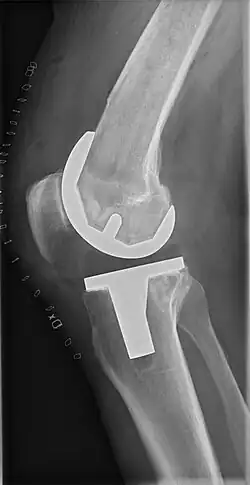

![]() |

Angles commonly measured before knee replacement surgery: |

To indicate knee replacement in case of osteoarthritis, its radiographic classification and severity of symptoms both should be substantial. Such radiography should consist of weightbearing X-rays of both knees: AP, lateral, and 30 degrees of flexion. AP and lateral views may not show joint space narrowing, but the 30-degree flexion view is most sensitive for narrowing. Full-length projections also are used in order to adjust the prosthesis to provide a neutral angle for the distal lower extremity. Two angles used for this purpose are:

- Hip-knee-shaft angle (HKS),[14] an angle formed between a line through the longitudinal axis of the femoral shaft and its mechanical axis, which is a line from the center of the femoral head to the intercondylar notch of the distal femur.[16]

- Hip-knee-ankle angle (HKA),[15] which is an angle between the femoral mechanical axis and the center of the ankle joint.[16] It is normally between 1.0° and 1.5° of varus in adults.[17]